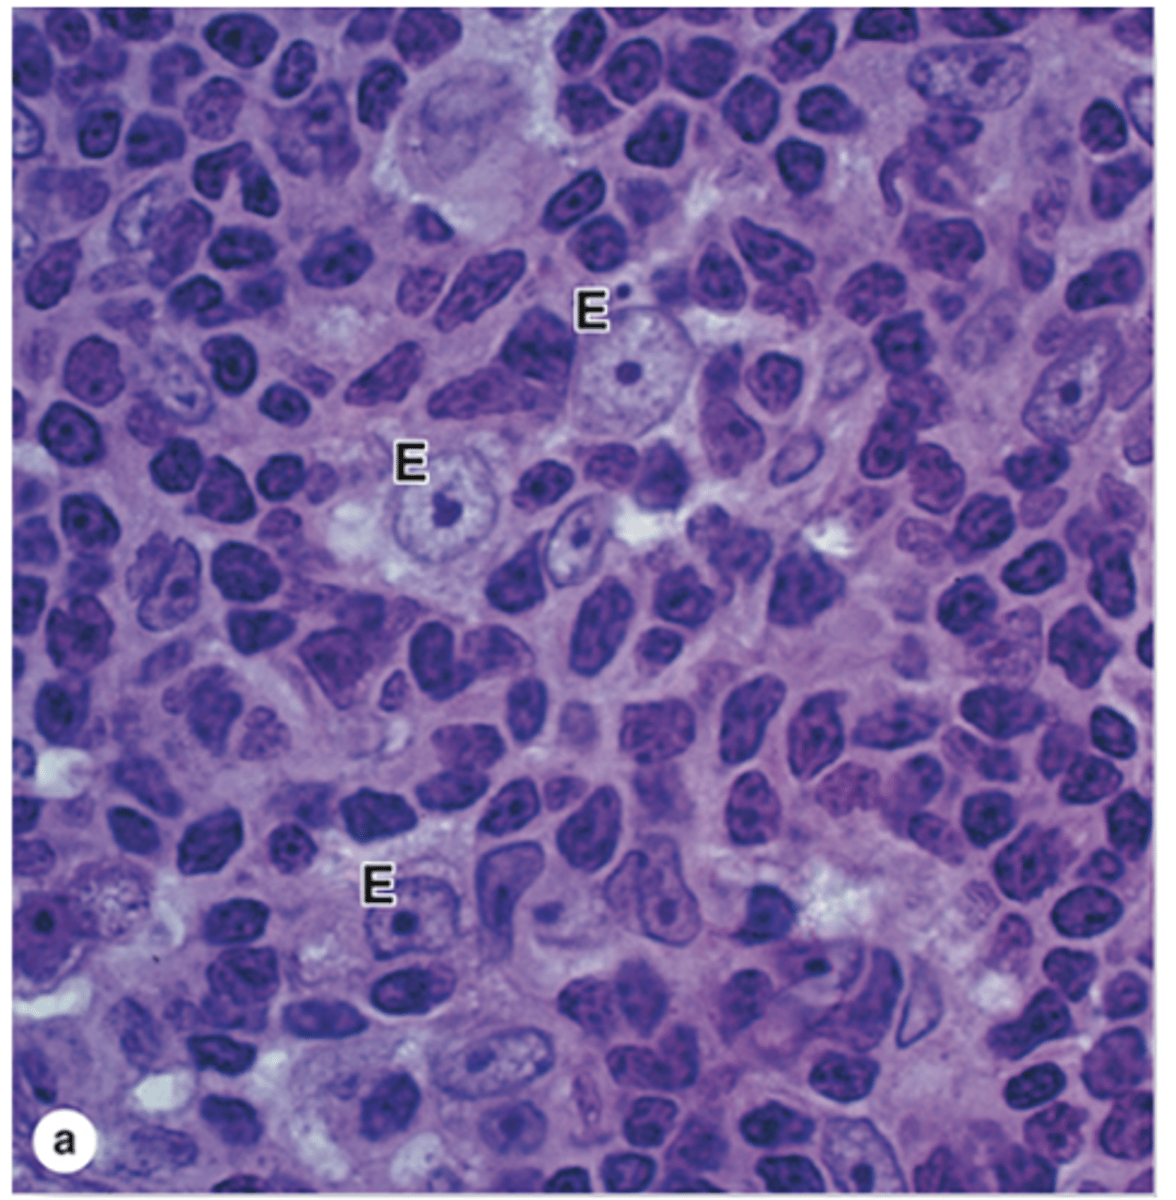

What are the three types of thymic epithelial cells in the cortex?

1. Squamous TECs (type I epithelioreticular cells)

2. Stellate TECs (type II epithelioreticular cells)

3. Type III epithelioreticular cells

What do the processes of Stellate TECs (type II epithelioreticular cells) contain?

Keratin tonofilaments

How are Stellate TECs (type II epithelioreticular cells) connected to one another?

They are joined by desmosomes.

What structure do Stellate TECs (type II epithelioreticular cells) form to support macrophages and developing lymphocytes?

A cytoreticulum (since the thymus lacks reticular fibers).

What antigen-presenting molecules do Stellate TECs (type II epithelioreticular cells) express?

MHC class I and MHC class II molecules.

What do Stellate TECs secrete to aid immune cell maturation?

Cytokines (promote T cell development)